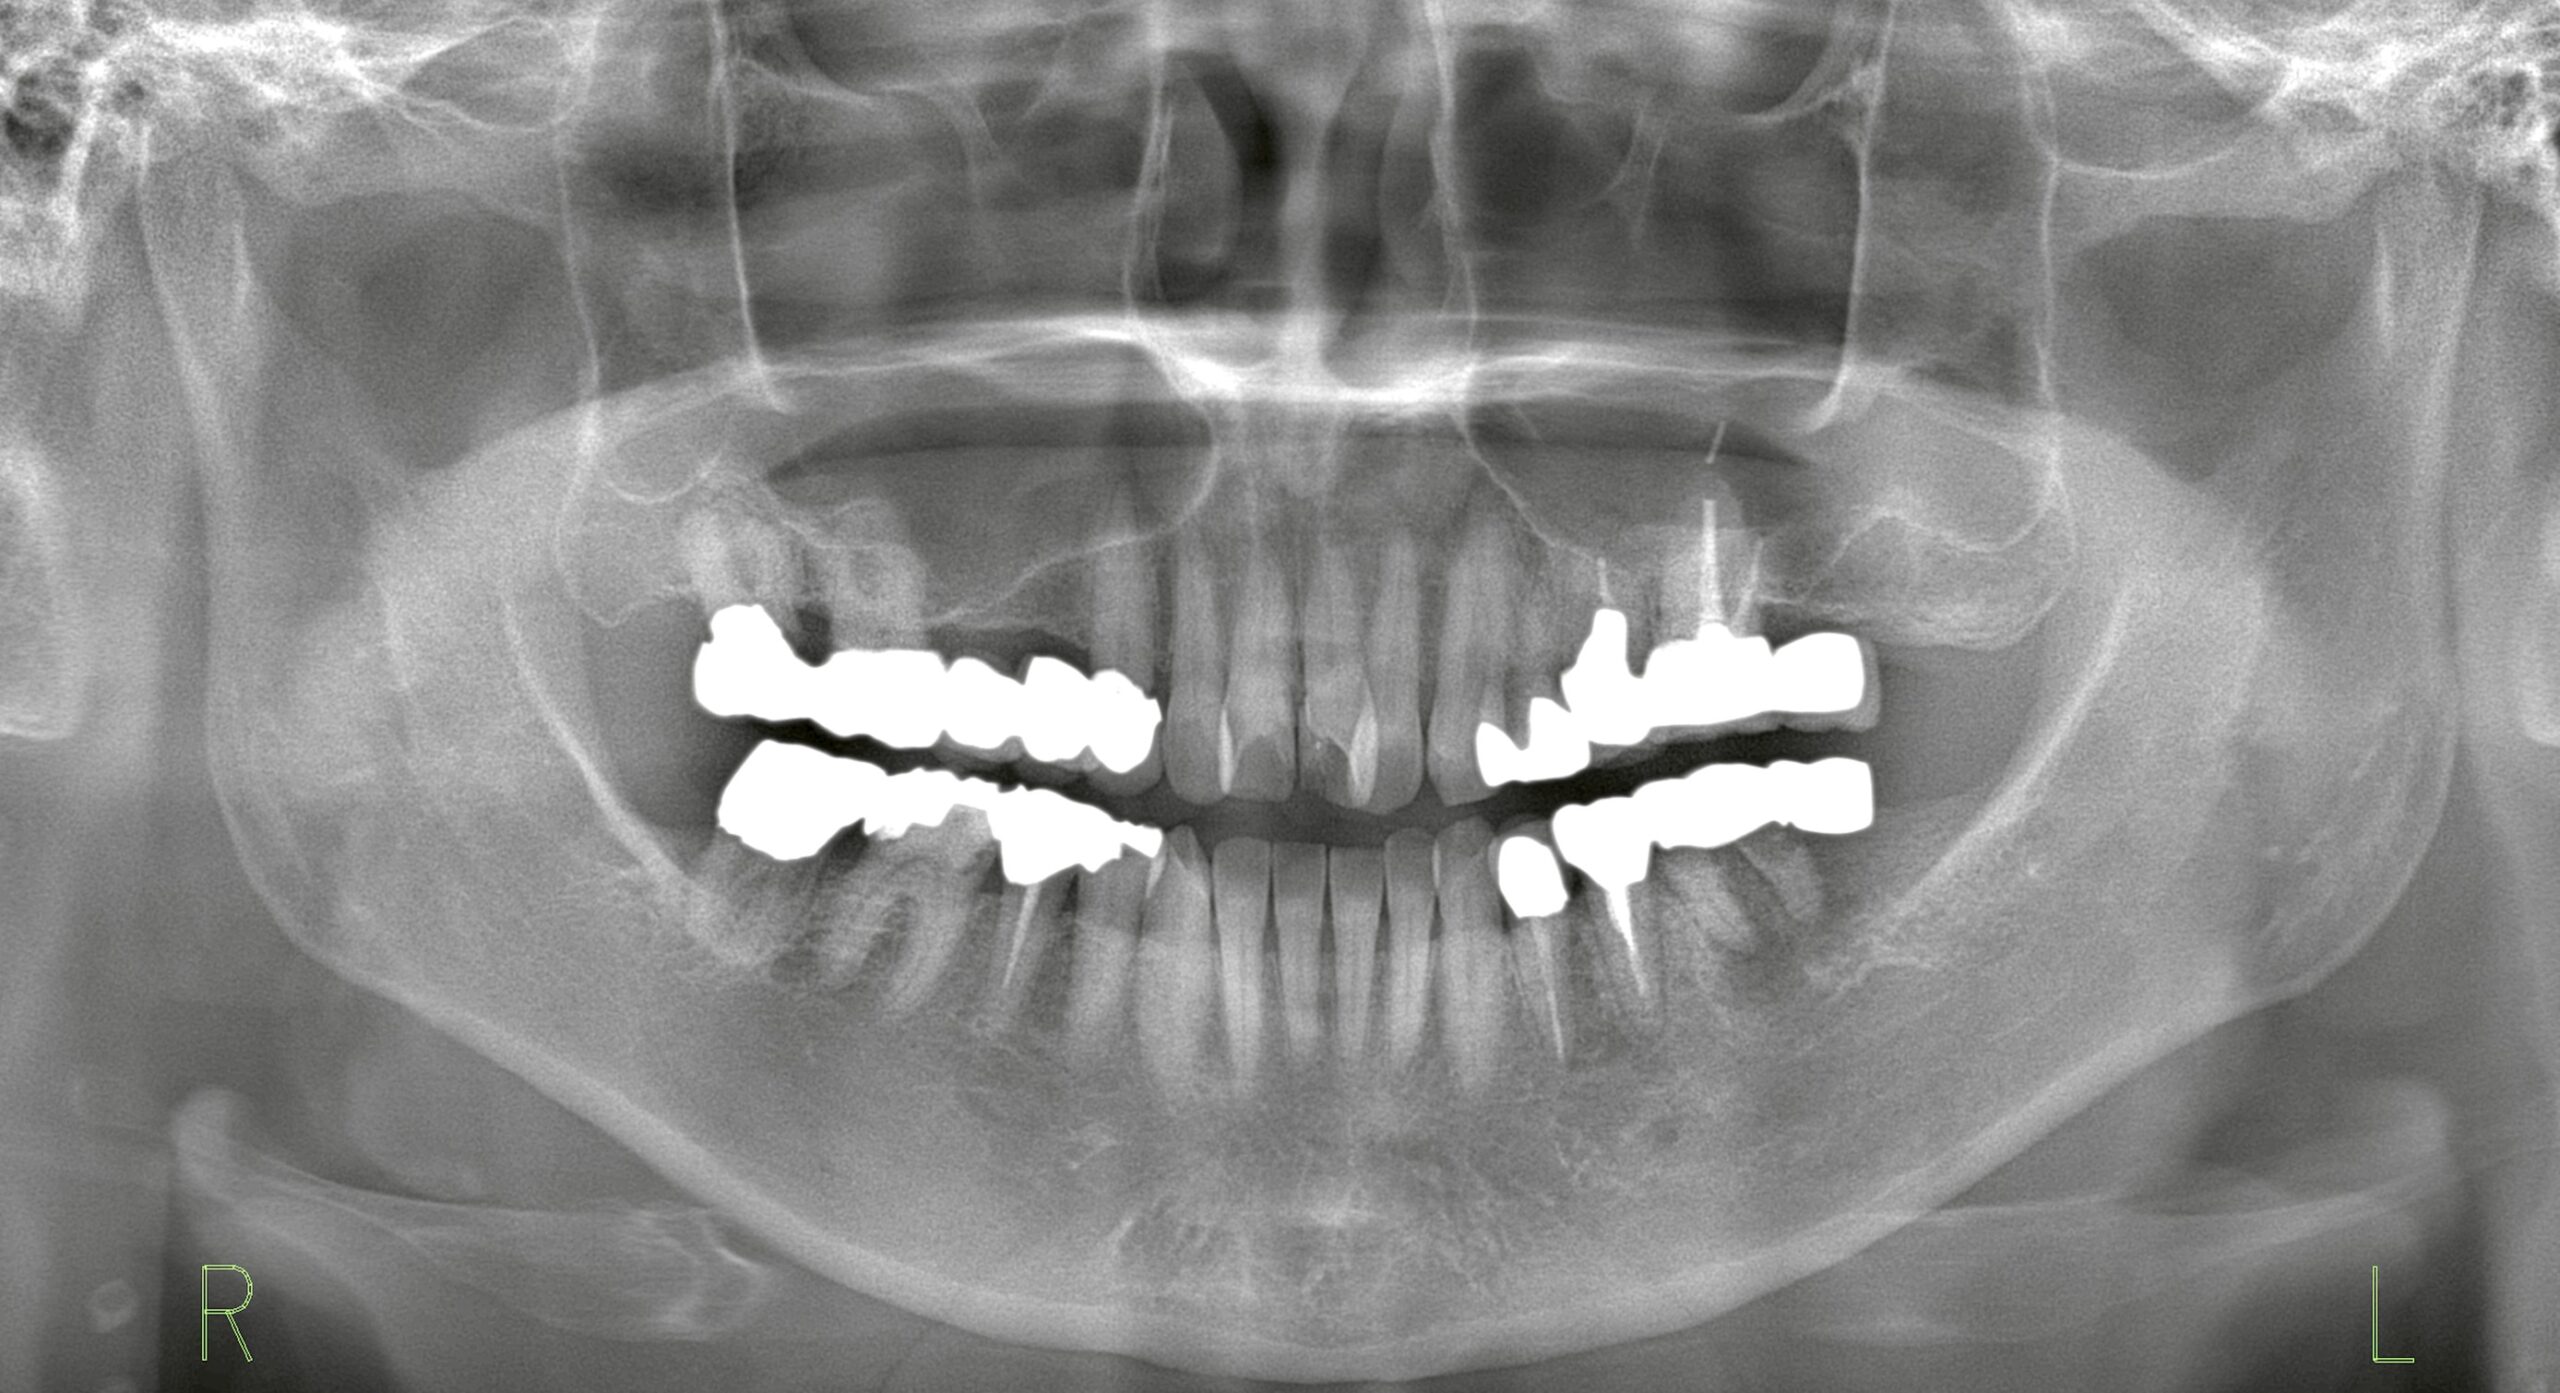

初診時のレントゲン

支台歯に動揺と排膿を認め、延長ブリッジは破折していました。延長ブリッジは「失活歯を支台として負担がかかる」ため、破折や歯周病リスクが高い治療方法の一つです。今回は抜歯が適応となり、延長ブリッジを撤去しました。